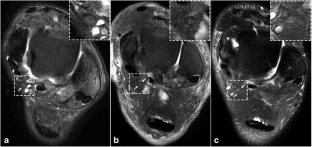

• Tibial nerves in patients with DPN showed T2 hyperintensity and enlargement.

• Tibial nerves in patients with DPN had an increased T2 value.

Wang D, Zhang X, Lu L et al (2015) Assessment of diabetic peripheral neuropathy in streptozotocin-induced diabetic rats with magnetic resonance imaging. Eur Radiol 25:463–471